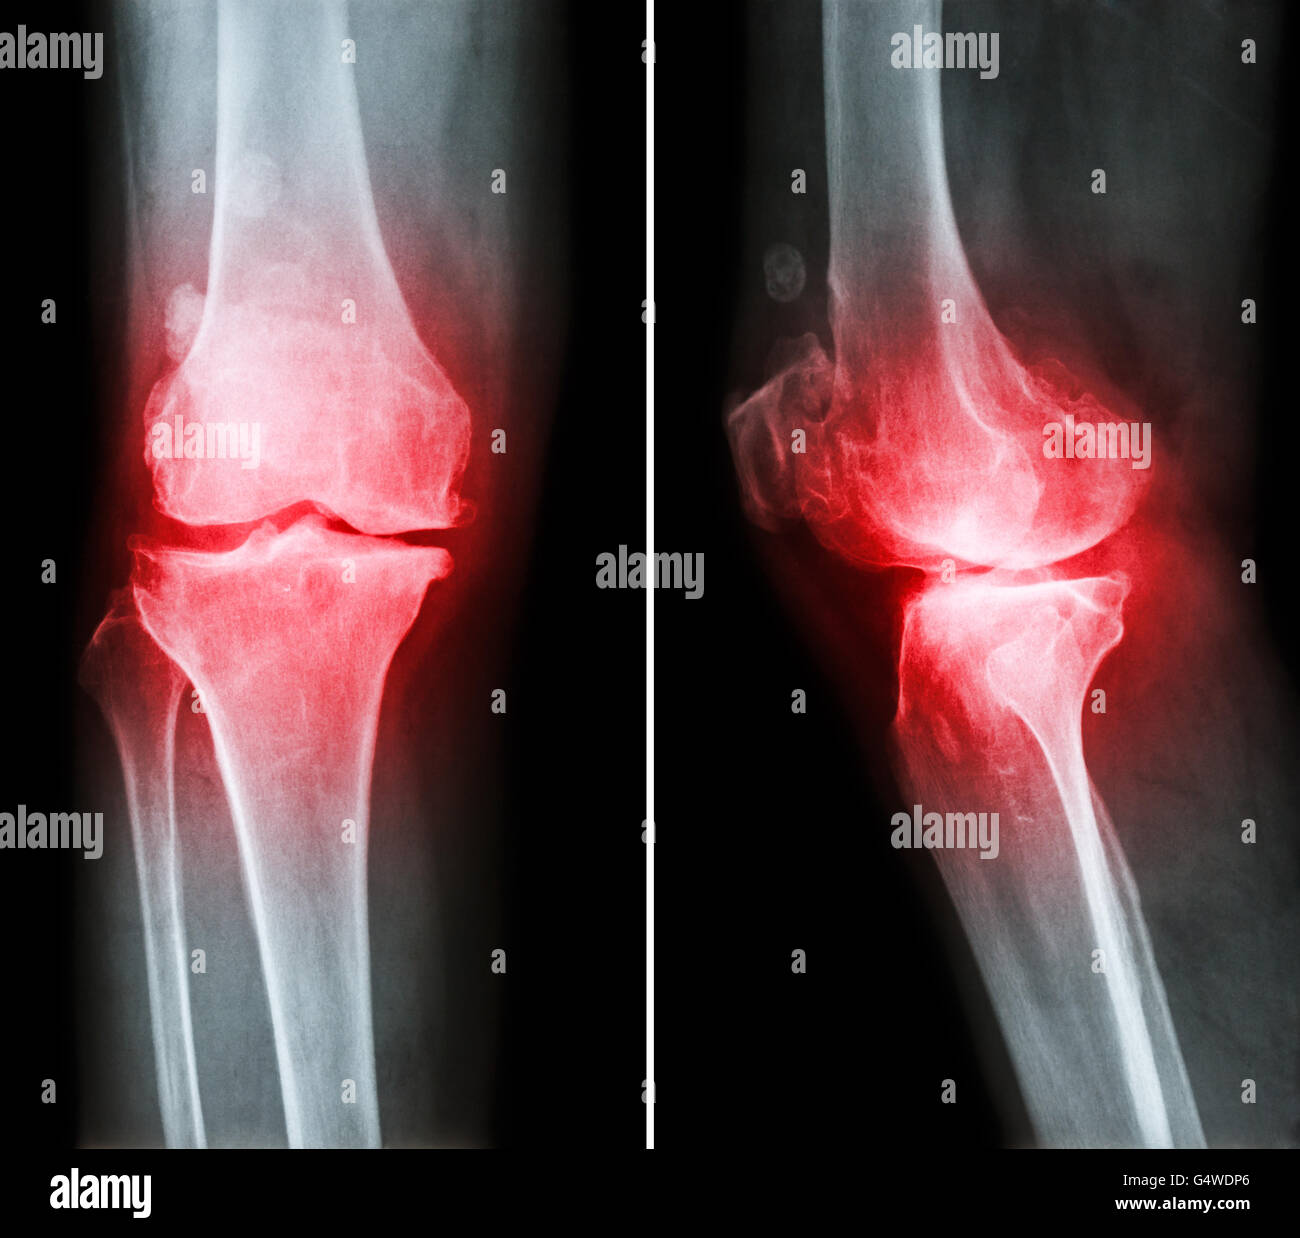

L'arthrose du genou . film x-ray ( genou - antérieure et postérieure vue latérale ) montre l'espace mixte étroit éperon ) , ('ostéophyte Banque D'Imageshttps://www.alamyimages.fr/image-license-details/?v=1https://www.alamyimages.fr/photo-image-l-arthrose-du-genou-film-x-ray-genou-anterieure-et-posterieure-vue-laterale-montre-l-espace-mixte-etroit-eperon-osteophyte-106280446.html

L'arthrose du genou . film x-ray ( genou - antérieure et postérieure vue latérale ) montre l'espace mixte étroit éperon ) , ('ostéophyte Banque D'Imageshttps://www.alamyimages.fr/image-license-details/?v=1https://www.alamyimages.fr/photo-image-l-arthrose-du-genou-film-x-ray-genou-anterieure-et-posterieure-vue-laterale-montre-l-espace-mixte-etroit-eperon-osteophyte-106280446.htmlRFG4WDP6–L'arthrose du genou . film x-ray ( genou - antérieure et postérieure vue latérale ) montre l'espace mixte étroit éperon ) , ('ostéophyte